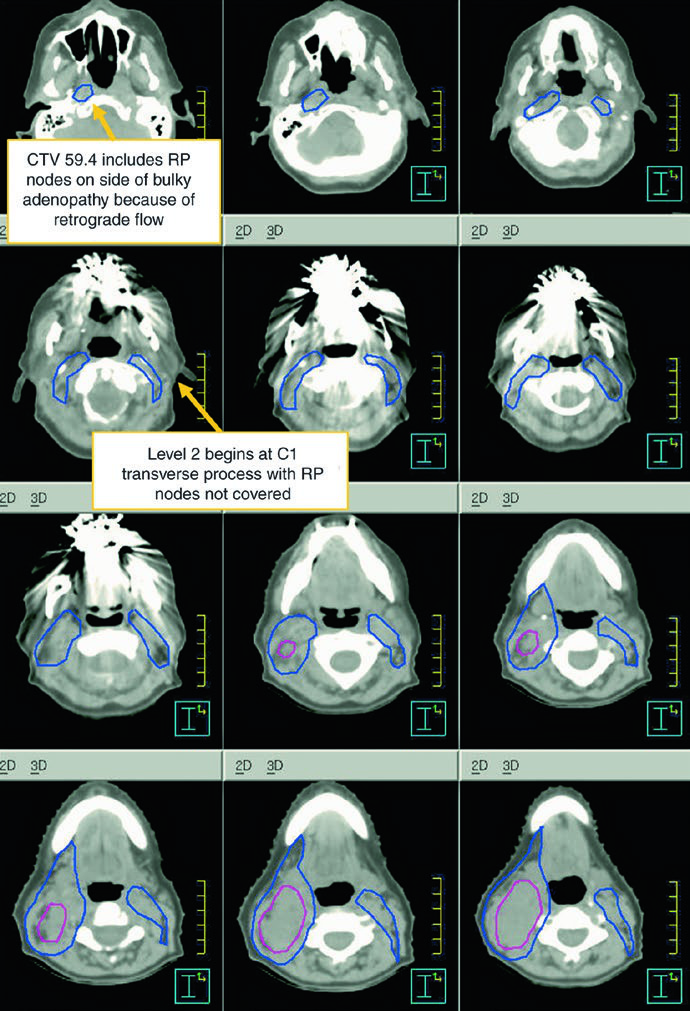

The subclinical primary CTV should cover the whole larynx from the bottom of the thyroid notch to the first tracheal ring, or farther inferiorly when needed. The subclinical nodal CTV should include at least levels II-IV and, in many cases, level VI. In the elective node-negative neck, the superior extent of level II stops where the posterior belly of the digastric crosses the internal jugular vein, corresponding to the caudal edge of the lateral process of C1. In the node-positive neck, level II should extend to the skull base and include the ipsilateral retrostyloid nodes.

| CTV 54-60a | Should encompass the entire GTV. Includes the entire larynx, from the bottom of the hyoid or the top of the thyroid notch to the bottom of the cricoid cartilage, with further inferior extension when needed. High-risk nodal regions include levels II-IV and the retrostyloid space on the involved node-positive neck. In the node-positive neck, level II should be treated to the base of skull. Level VI should be included if there is subglottic extension or a trach. |

| CTV 54b | Levels II-IV of the uninvolved neck. In the node-negative neck, the superior border of level II stops where the posterior belly of the digastric crosses the internal jugular vein, or at the caudal edge of the lateral process of C1. Levels IB and V are not included unless there is gross disease at those levels. Retropharyngeal nodes may be covered at physician discretion on the side of bulky adenopathy because of retrograde flow. Level VII coverage is recommended for subglottic extension or hypopharyngeal involvement. |

Levels IB and V are not elective by default and are only included when gross disease is present there. Retropharyngeal nodes may be covered on the side of bulky adenopathy at physician discretion. Level VII is recommended for subglottic extension or hypopharyngeal involvement. That is one of the most useful parts of the chapter because it turns abstract spread patterns into concrete cranial and caudal borders.

The figure caption adds two good reminders. In that example, level IB was included by the treating physician even though it can be omitted. The upper trachea was not treated, but the text notes that it should be included when indicated. That is a useful warning against copying a figure without rechecking the anatomy.